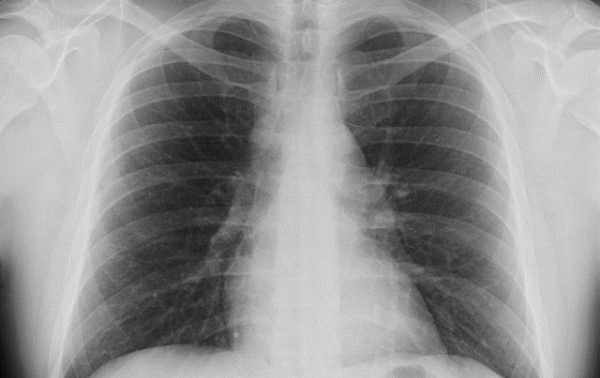

Non riuscendo più a respirare, l’uomo si è infine recato al pronto soccorso di Borgomanero. Qui, dopo gli esami di rito, gli hanno comunicato che aveva una polmonite in corso, con interessamento delle transaminasi.